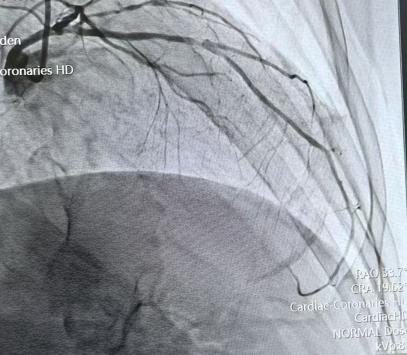

传统治疗主要依靠冠脉造影,但造影只能提供二维平面图像,就像只看一张黑白照片,很难看清血管壁内部的情况:比如斑块是什么性质?血管真实直径多大?管腔面积剩多少?病变边界在哪?这些关键信息一旦不清,支架放得准不准、贴不贴壁,就容易打折扣。

这次接受手术的患者,因反复胸闷、胸痛入院。经冠脉造影和血管内超声检查,确诊为左主干—前降支全程弥漫性病变。具体来看:

◆左主干体尾部狭窄约 50%,血管内最小管腔面积 3.35mm^2(正常应大于6mm^2)

◆前降支中段狭窄最重达 90%

(术前)